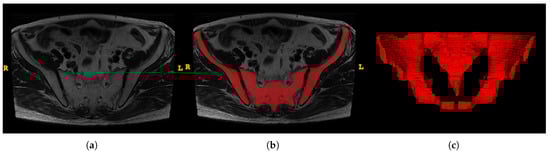

ITK-SNAP software (version 3.8.0, www.itksnap.org) was utilized to obtain the region of interest (ROI) for further analysis [16]. The ROIs were carefully delineated along with the pelvis (Figure 3). Two trained surgeons (Z.S., W.Y.H.) independently conducted segmentation, and two experienced radiologists (J.J.L., H.D.X.) were introduced for supervision.

Figure 3.

An example of manual segmentation of pelvis in MRI. (a) Bilateral ilium and sacrococcyx in T2-weighted images; (b) Manual segmentation on the same axial slice (Bilateral ilium and sacrococcyx are highlighted in red); (c) reconstruction of the pelvis.

To normalize the different scan settings between MR images of patients, the images and annotations were resampled to 1.5 mm×1.5 mm×1.5 mm voxel spacing using the SimpleITK library [17,18], and were then converted to the Neuroimaging Informatics Technology Initiative (NIfTI) format. To avoid the interference of the grayscale texture and irrelevant tissue, and for the the neural network model to pay attention to the bone structure and pelvic distance within the ROI, we set the voxel value to 0 for the non-ROI area, and to 1 for the bilateral ilium and the sacrococcyx. All images are padded to the same size, with a value of 0.